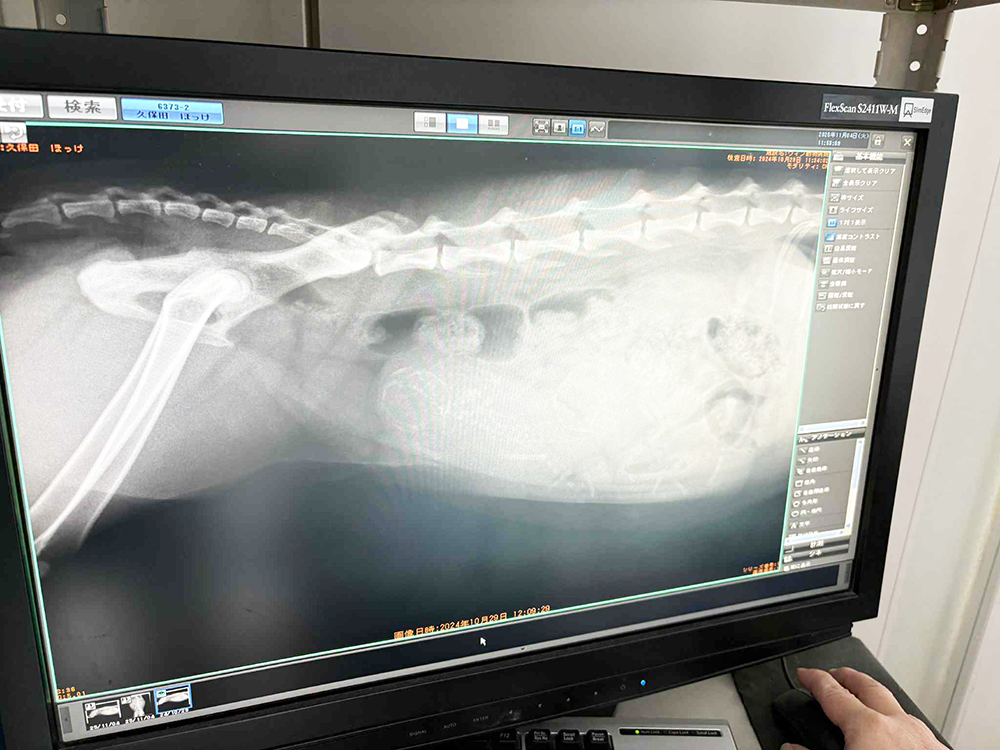

3匹いました。

とにかくいつもの通り、全員が元気ででてきてほしいです。